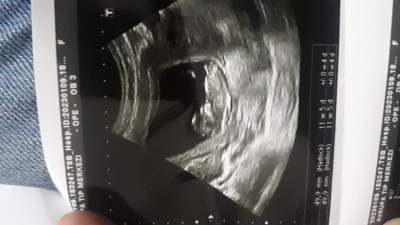

iyi aksamlar arkafaslR tam 11 haftaligim ultrasonda 11+5 tahmin alabilirmiym

Crl 49 mu kız diyorum

Kız cnm hayırlısı olsun

Erkek bebek bence ☺️